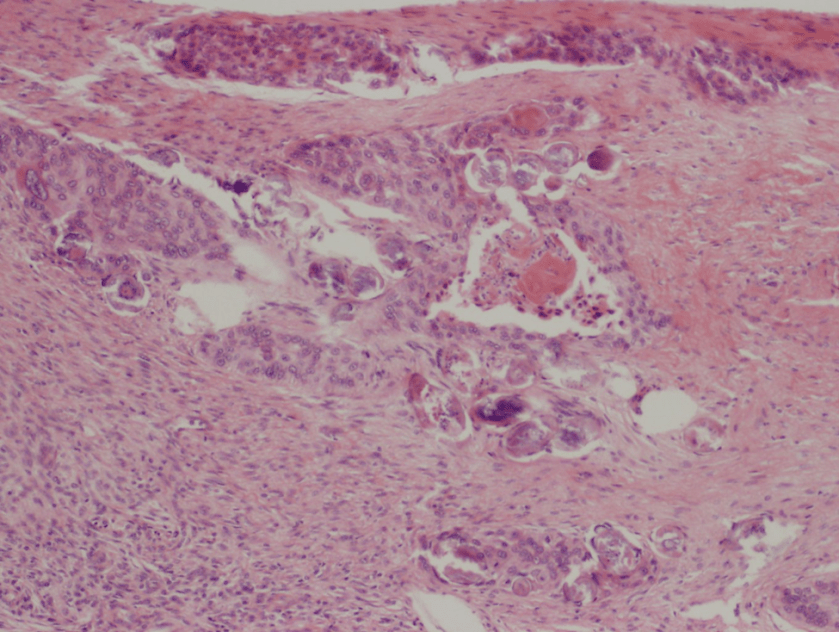

- Skin biopsy: slight epidermal hyperplasia with follicular dilatation, mild vascular ectasia, and focal erythrocyte extravasation. Negative for organisms.

- Gram stain: rare budding yeast forms seen

The gram smear made from skin biopsy tissue for bacterial culture displayed rare broad-based budding yeast forms, consistent with Blastomyces dermatiditis.

The gold standard for diagnosis is culture or cytopathology/histology. However, the organism is a slow grower, which can take 2-4 weeks, and may fail to grow in one-third of cases. On culture at room temperatures (25-30°C), the mold form appears wrinkled and waxy and is cream to tan in color. Microscopically, they form septate hyphae with short or long conidiophores bearing small round to pear-shaped conidia (2-10 microns). This arrangement of the mold is described as a “lollipop” appearance. At 35-37°C, the fungus is a yeast (8-10 microns) with classic broad-based budding and double contoured walls.